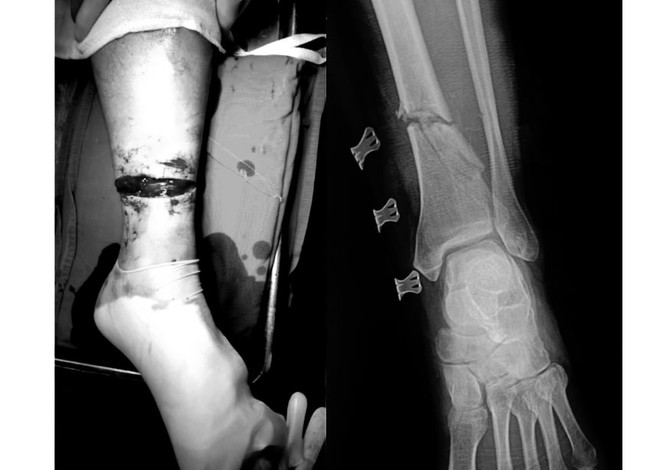

Tai nạn khi cắt cỏ, người đàn ông bị lưỡi cưa cắt đứt chân ảnh 1Chân của bệnh nhân sau khi bị lưỡi cưa cắt qua. (Ảnh: PV/Vietnam+)

Bệnh nhân tên B.V.L (56 tuổi, ở Hòa Bình) nhập viện trong tình trạng vết thương hở đứt 3/4 chu vi cẳng chân trái, chảy nhiều máu. Bệnh nhân bị mất vận động cổ chân và các ngón chân, gãy hở xương, đứt hoàn toàn các gân cơ khu trước và sau cẳng chân, đứt bó mạch chày sau, chày trước.

Bác sỹ Hoàng Minh Thắng - Khoa Phẫu thuật Chi trên và Y học thể thao cho biết, người bệnh đã được cố định ngoài xương chày, nối gân, thần kinh, nối động mạch chày trước, chày sau.

Hiện tại sau mổ, tình trạng bệnh nhân đã ổn định, đầu chi hồng ấm, mạch chày trước, chày sau rõ và đang được hướng dẫn tập phục hồi chức năng.